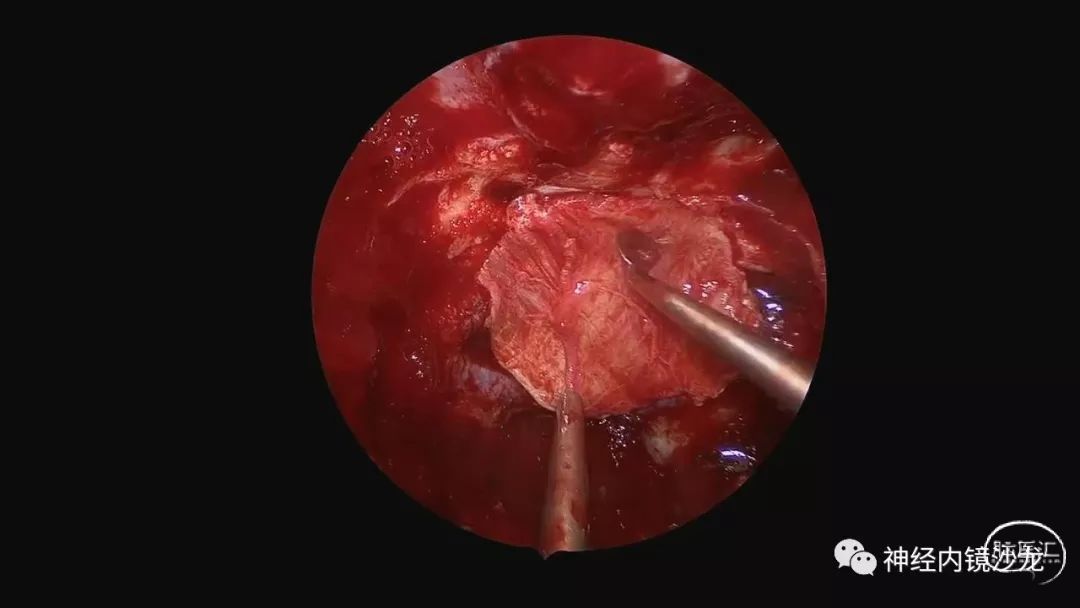

手术视频

从事神经外科十余年,擅长神经外科肿瘤诊治,尤其是神经内镜微创手术治疗垂体瘤、颅咽管瘤、脑膜瘤等颅底肿瘤